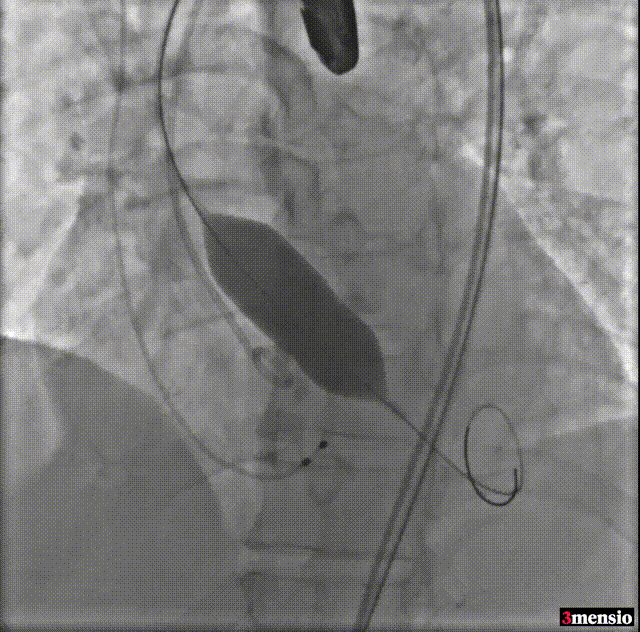

球囊预扩

预释放定位

瓣膜释放至工作位

工作位造影